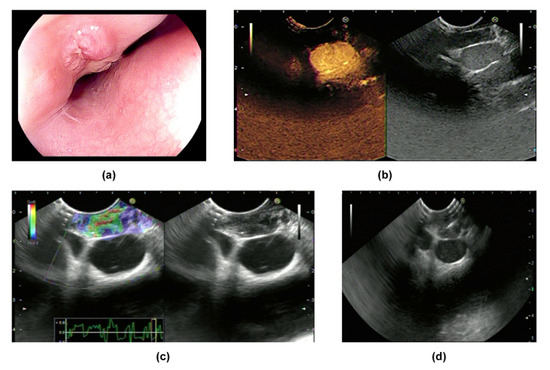

CH-EUS was performed in two cases in our research center. Both lesions featured hypo-enhancement compared with the surrounding tissues (Figure 1b and Figure 2b) (Table 2). Mechanically, hypo-enhancement reflects a deficiency of blood supply, which corresponds to Stage II or above when the lymph nodes undergo caseous necrosis. Caseous granuloma is always detected in infected lymph nodes which are in Stage II or a more severe stage. In fact, granuloma was found in Cases 1–4 which we will introduce later. Using elastography, images of two lesions were mainly green, showing that both lesions were soft (Figure 1c and Figure 2c) (Table 2). The characteristics of ET when using CH-EUS and elastography are worth further evaluation.

8. Case Reports

Figure 1. Manifestations of Case 1: (a) manifestations of the lesion according to EGD; (b) the lesion was hypo-enhanced according to CH-EUS; (c) the lesion was soft according to elastography; (d) EUS-FNA for the lesion.